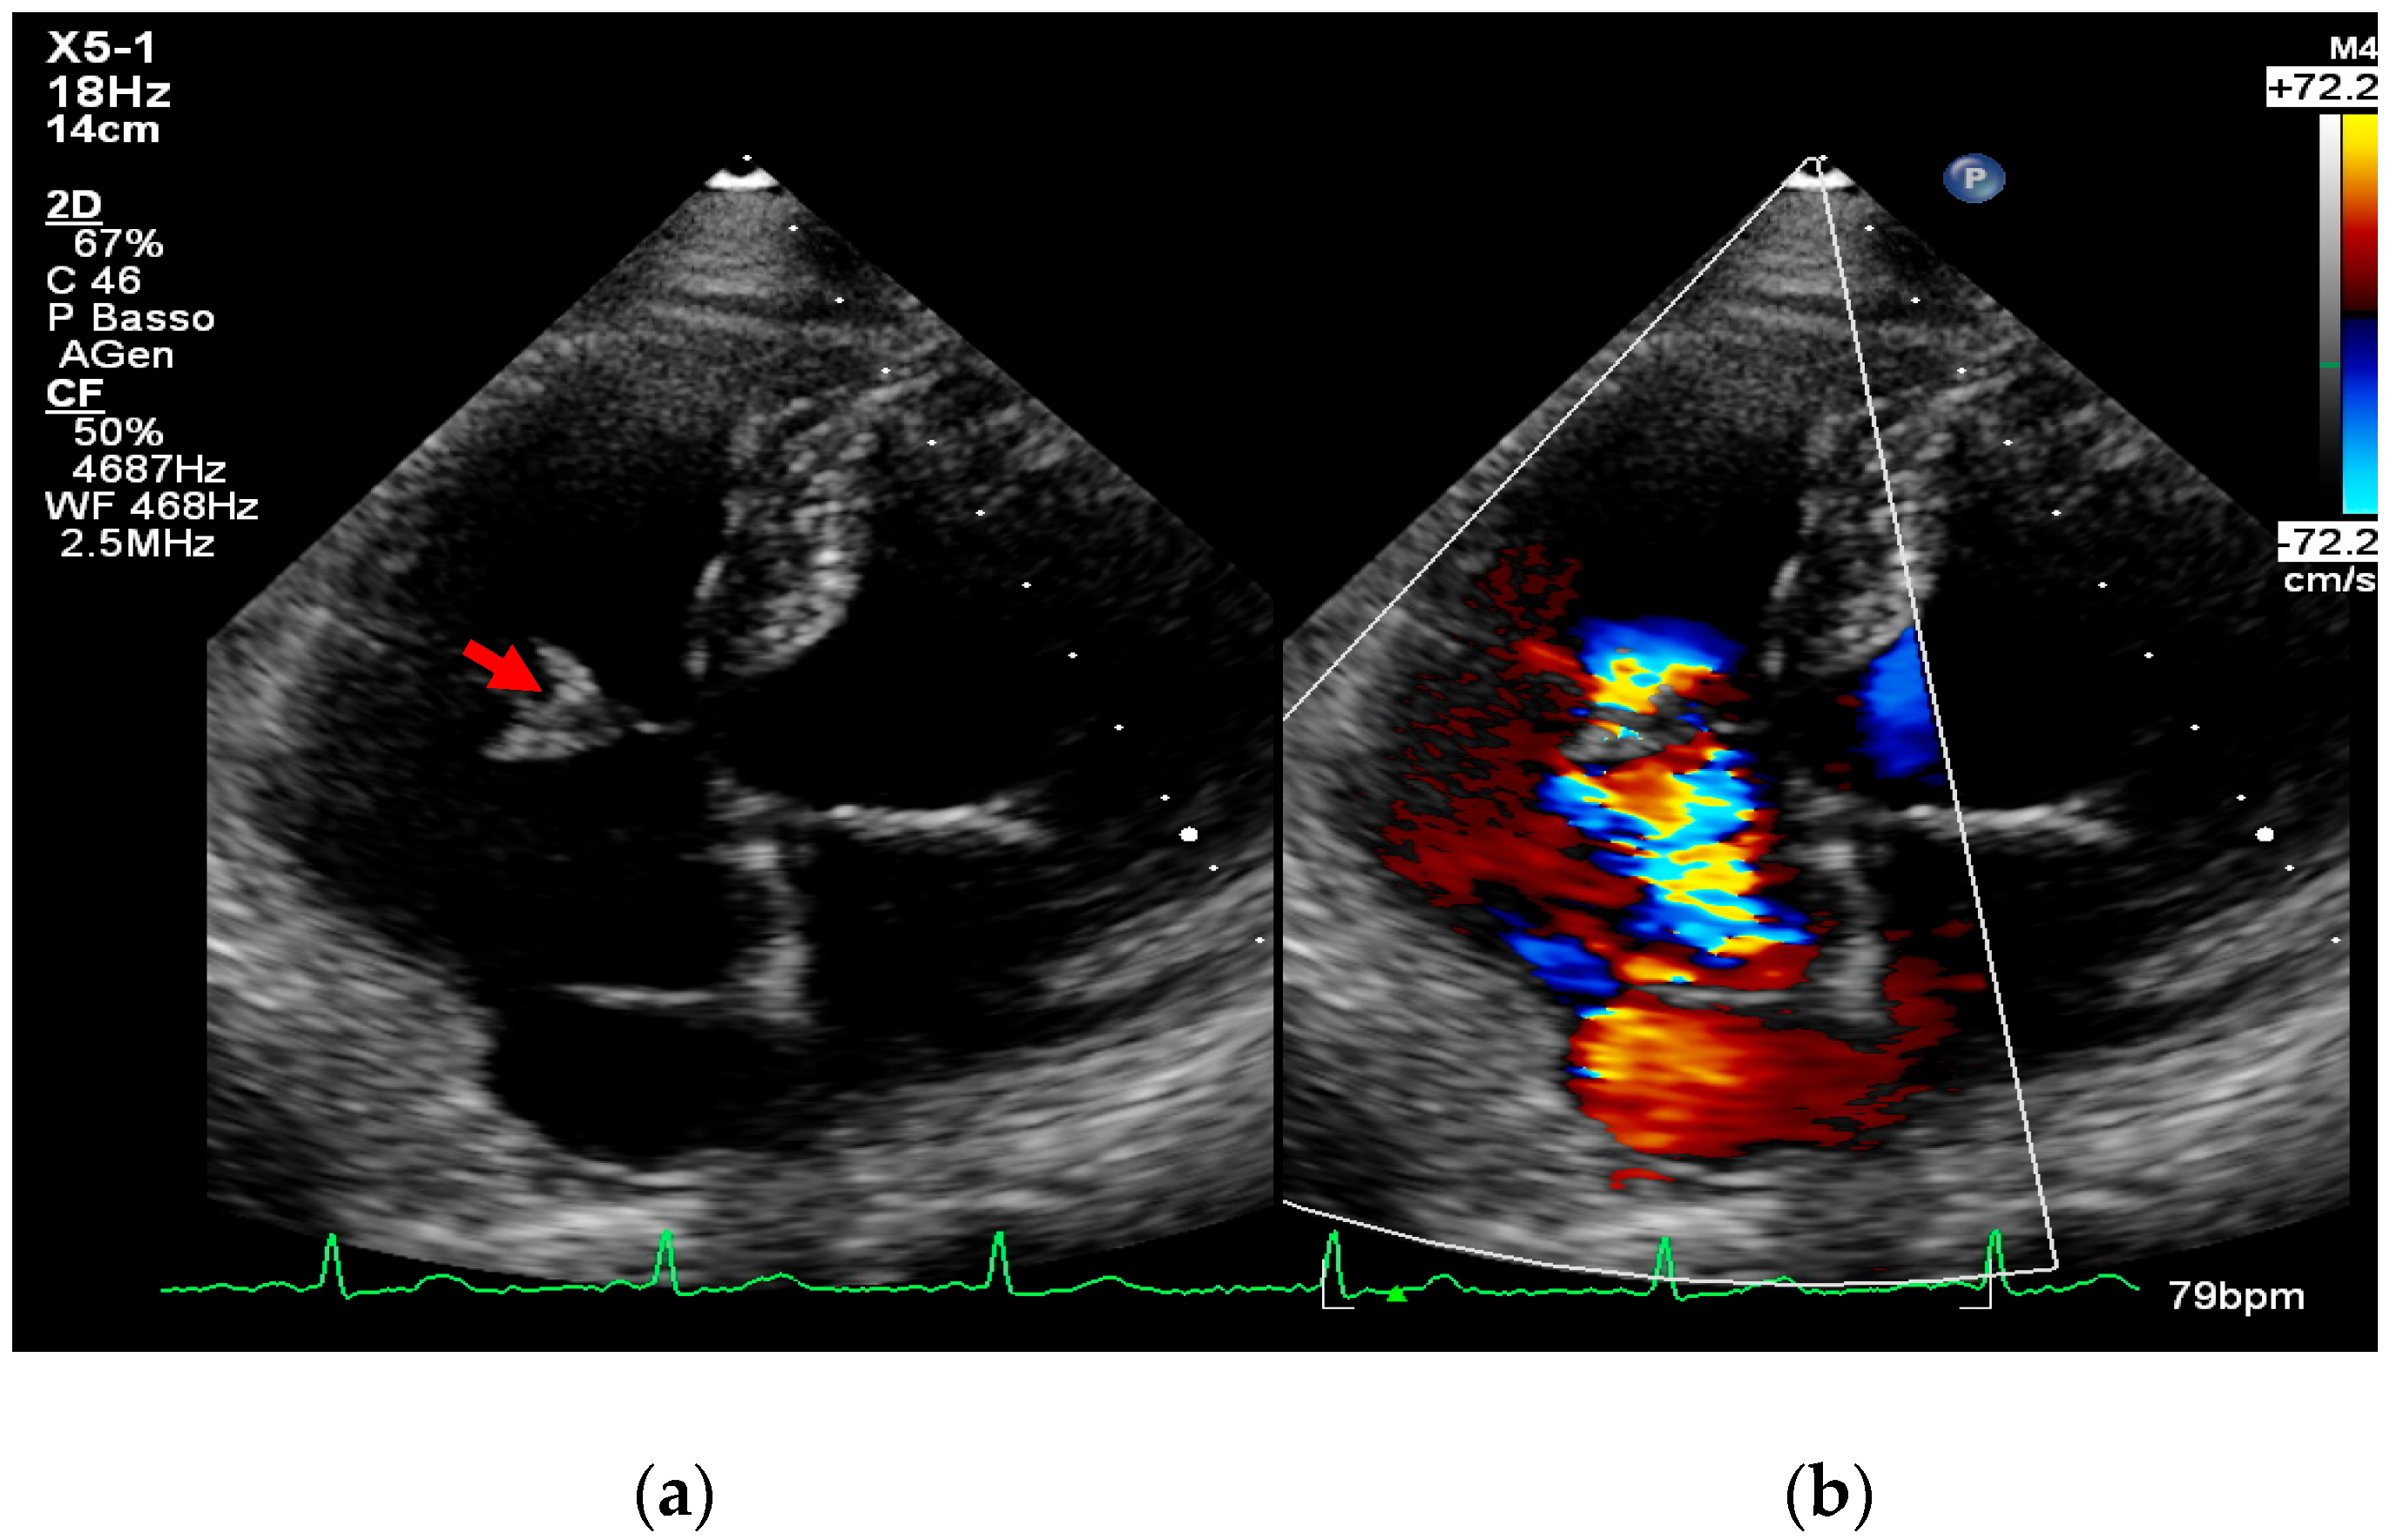

- intracardiac fistula, visualized as an abnormal communication between cardiac chambers or vessels, is often detected by using color Doppler.

- significant new valvular regurgitation compared with previous imaging, i.e., increase in regurgitant jet size, vena contracta width…